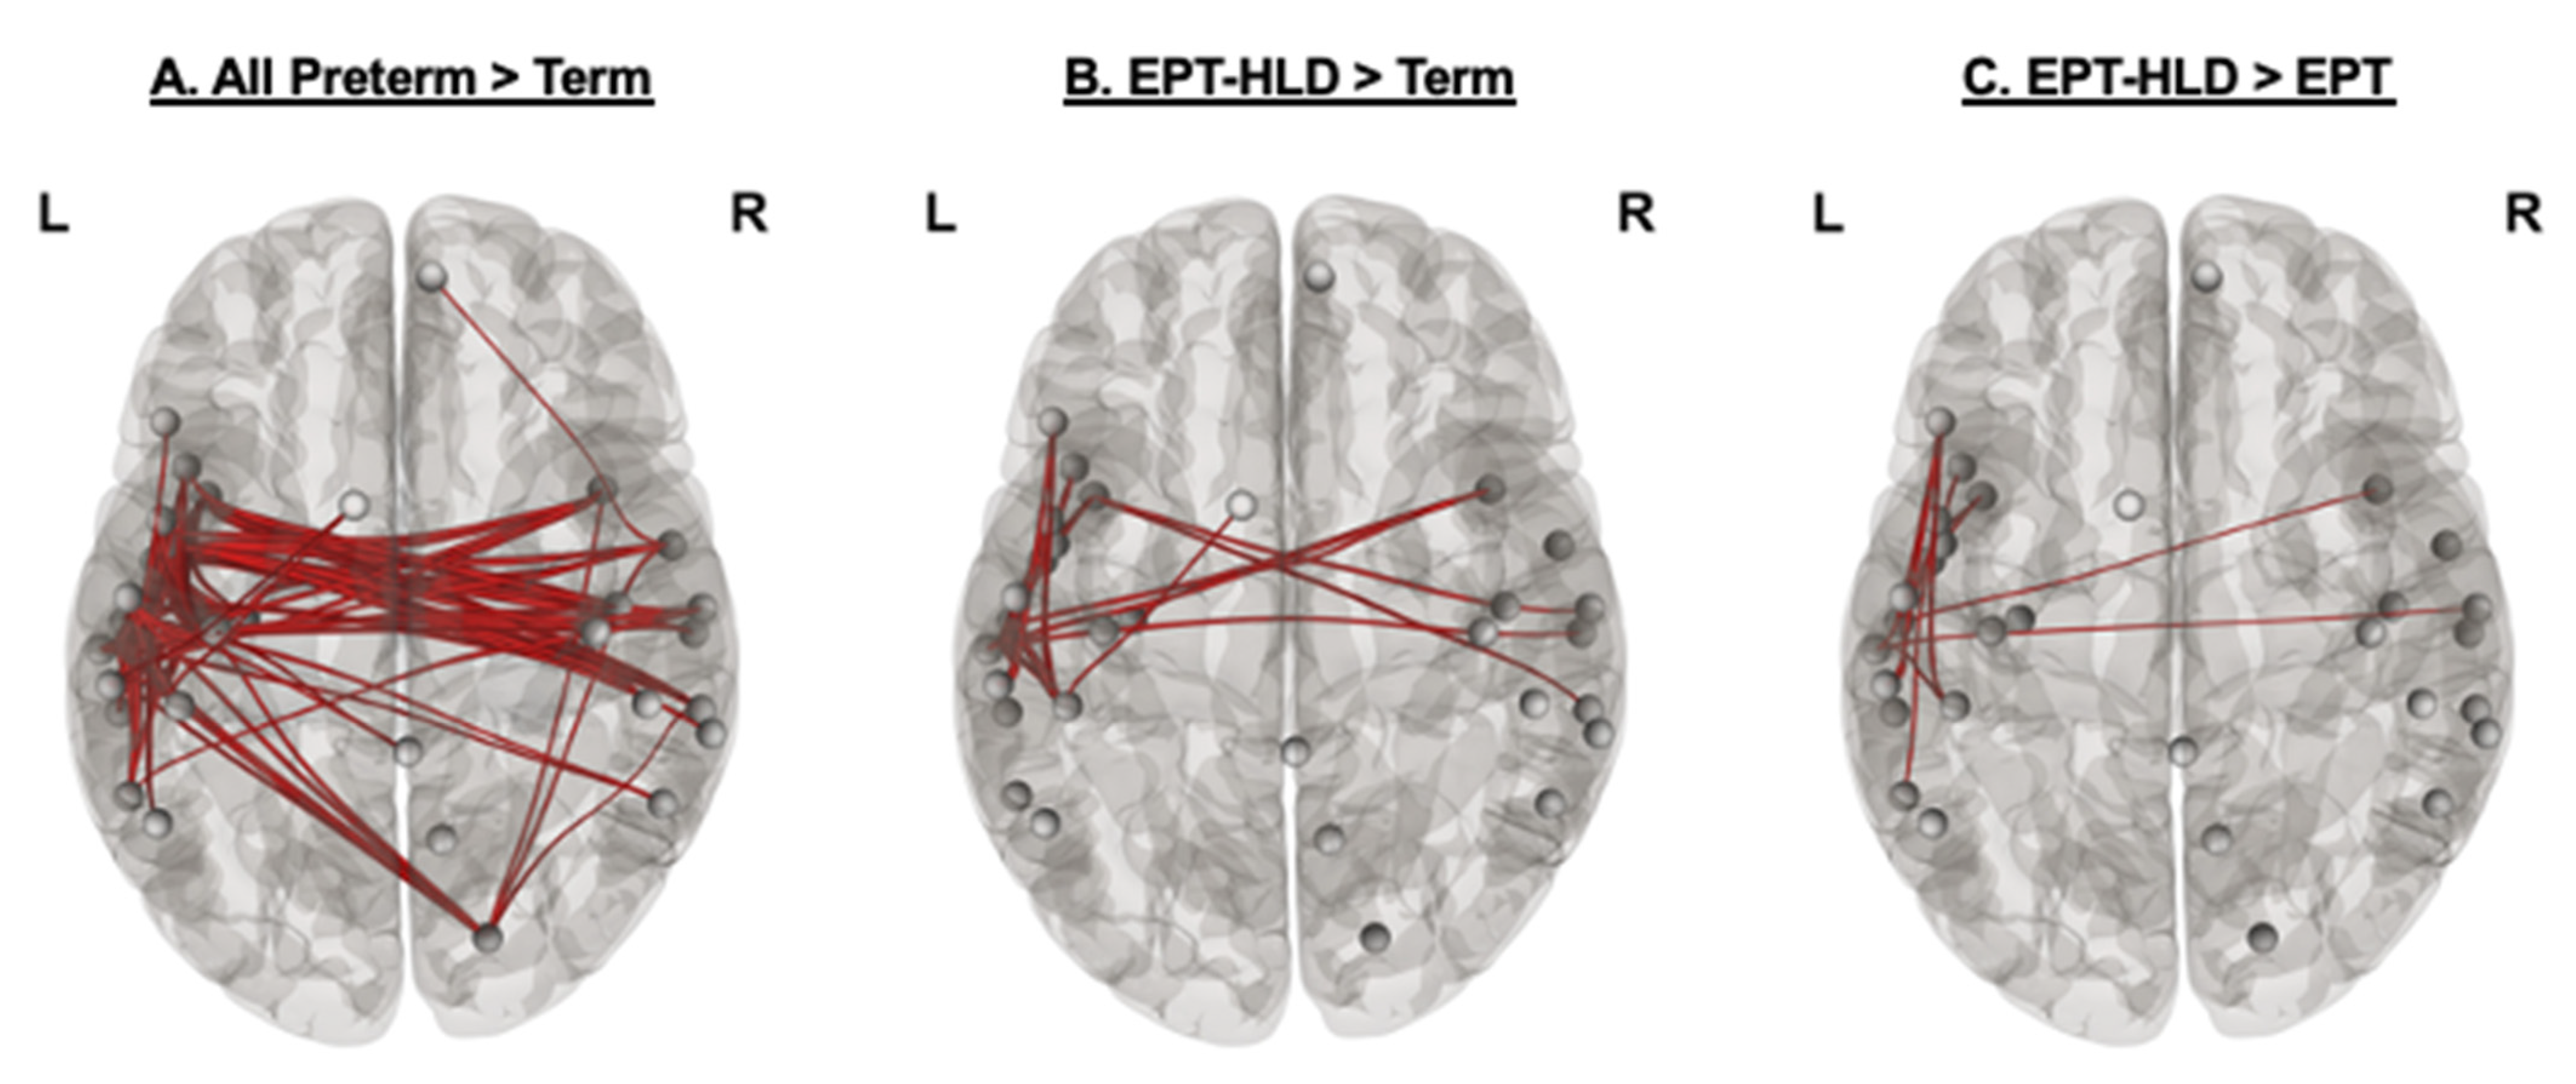

3.3. Functional Connectivity on Magnetoencephalography

3.4. Network Strength and Relation to Performance

3.4.1. All Extremely Preterm Children versus Term Children

3.4.2. Extremely Preterm Children without History of Language Delay or Deficit (EPT)

3.4.3. Extremely Preterm Children with History of Language Delay or Deficit (EPT-HLD)